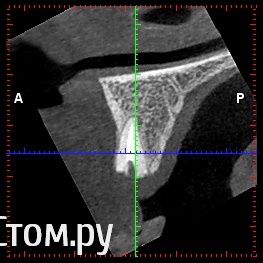

rezo47 Опубликовано 16 октября, 2014 Поделиться Опубликовано 16 октября, 2014 (изменено) Добрый день, возможно ли применение такой методики при такой клинике? Изменено 16 октября, 2014 пользователем rezo47 Ссылка на комментарий

Дмитрий Никитюк Опубликовано 16 октября, 2014 Автор Поделиться Опубликовано 16 октября, 2014 Добрый день, возможно ли применение такой методики при такой клинике?Одного КТ для обсуждения подобных вопросов мало, но ситуация более благоприятна, чем в случае из стартового сообщения. Давайте фото и описание случая, можно будет обсудить детально. По позиционированию имплантата: позиционируйте его более нёбно, чем это сделано в программе. 3 Ссылка на комментарий